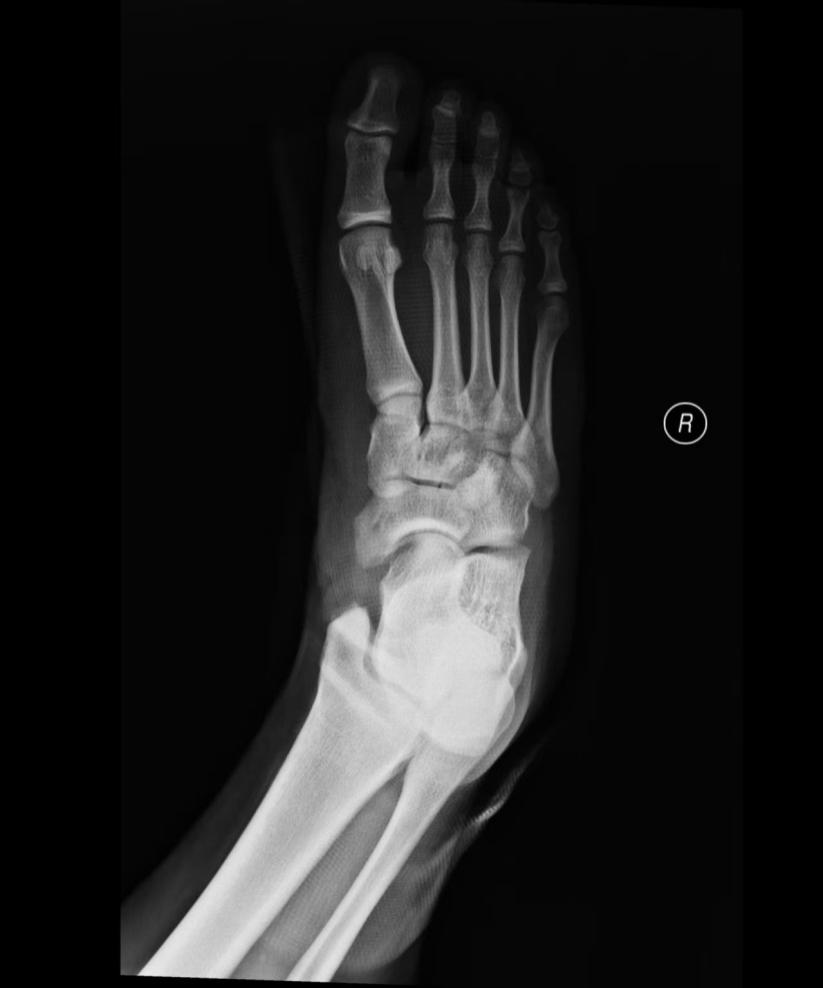

影像学证据:足部X光片是基础,能清晰显示副舟骨的存在、大小、形态及其与主舟骨的关系。MRI 则能进一步评估胫后肌腱及周围软组织的损伤、炎症水肿程度,为制定治疗方案提供关键依据。